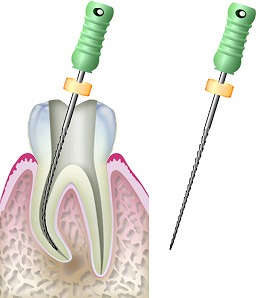

基本的には感染してしまった根っこの治療は歯の頭の方からアクセスして治療を行っていきます。

こんな風に感染した根っこの中をこの細い器具で掃除していくのです٩( ‘ω’ )و

しかし、このどうしても治りが悪かったり、被せ物が外せない事情があったりすると外科的にアプローチして原因の根っこを切除し、病巣もとってしまう方法が『歯根端切除 しこんたんせつじょ』なのです!